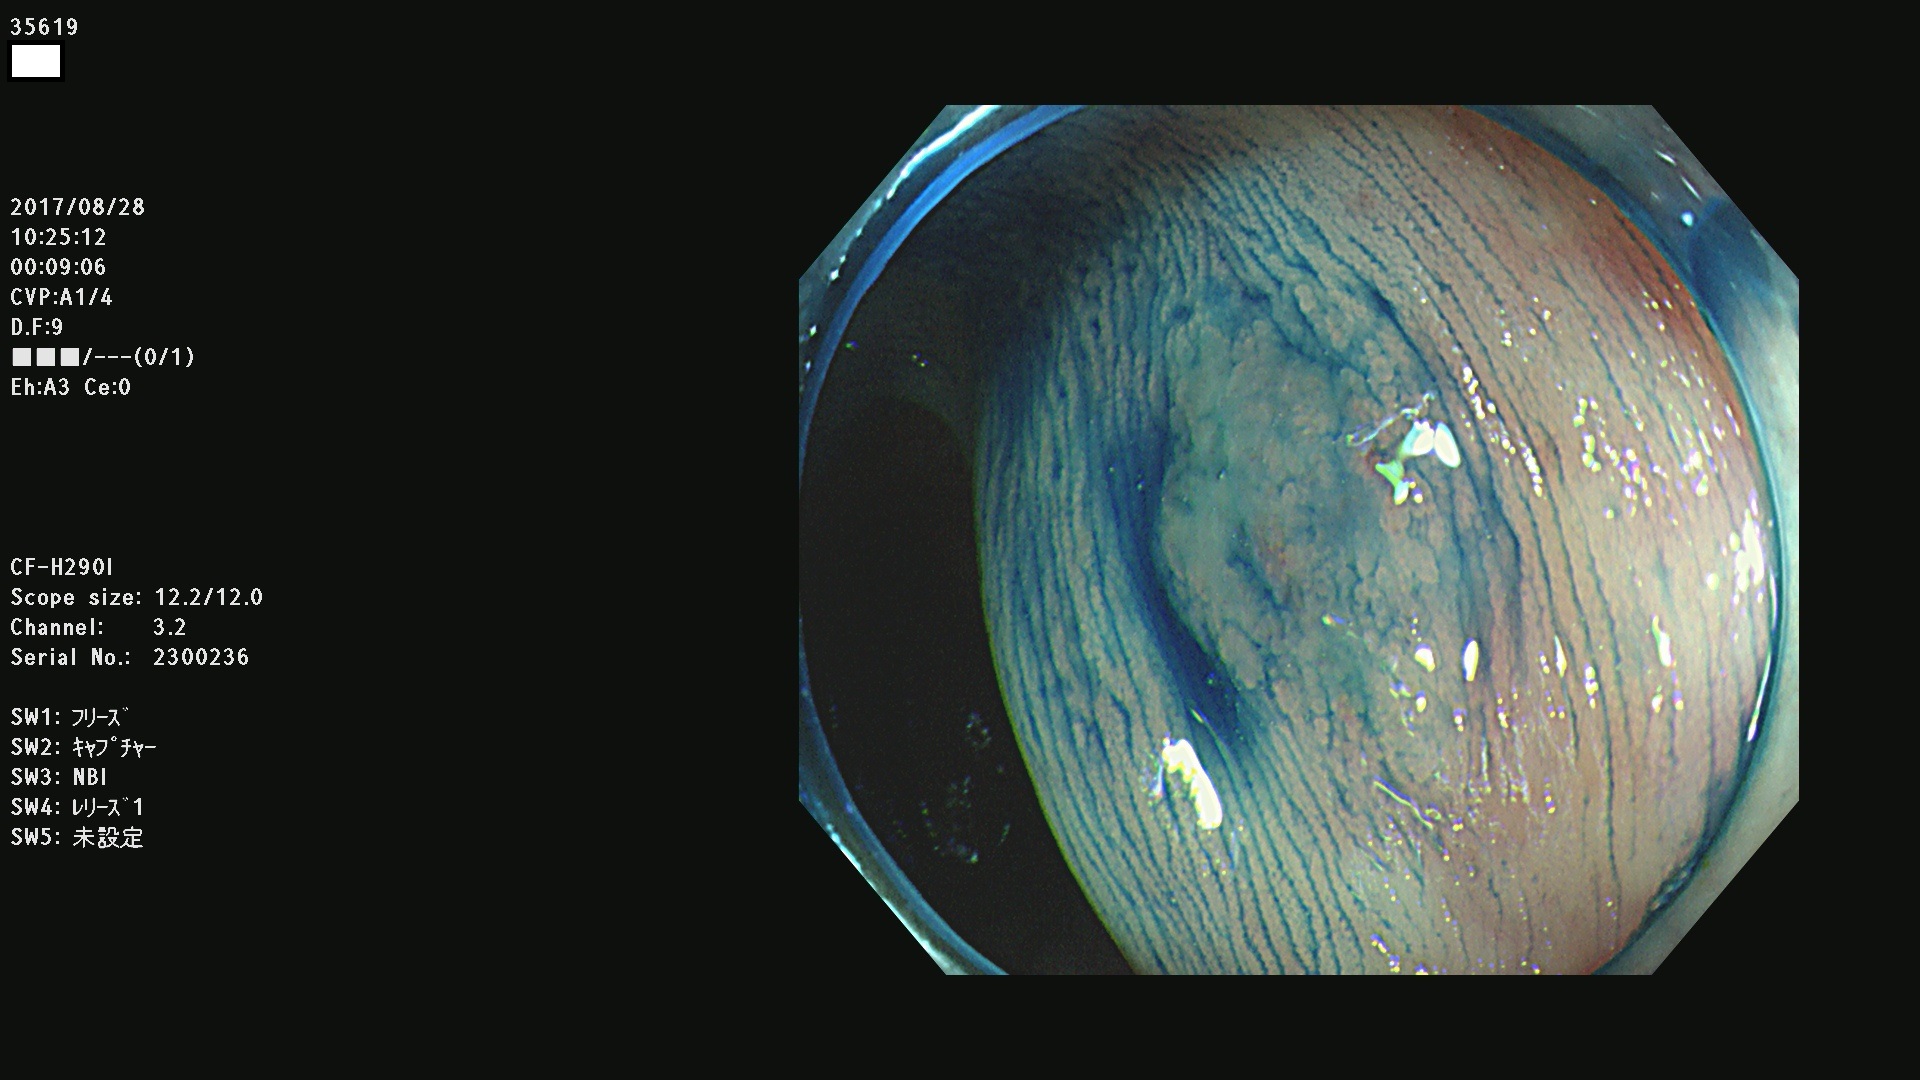

発見困難で危険性の高い平坦型病変(上記100名より抽出)

35600 35603 35604 35609 35612 35613 35614 35619(SSA/Pのみ) 35624 35625 35626 35627 35629 35630 35631 35633 35634 35635 35636 35638 35641 35642 35643 35644 35645 35646(SSA/Pのみ) 35648 35651(SSA/Pのみ) 35652 35653 35655 35656(SSA/Pのみ) 35659 35660 35664 35665 35667 35668 35669 35670 35671 35675 35678 35679 35680 35682 35684 35689(SSA/Pのみ) 35695 35696 35699